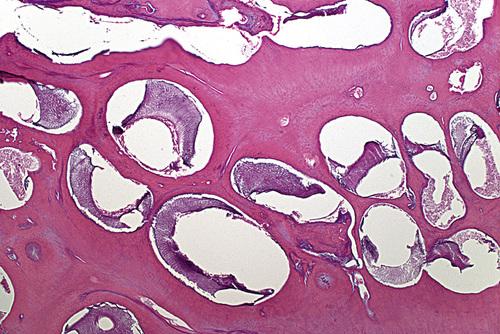

Odontogenic keratocyst (OKC) showing numerous odontogenic epithelial rests in the cyst wall.

nevoid basal cell carcinoma syndrome

Histopathologic Features

- keratocysts with a fibrous capsule having more:

- satellite cysts

- islands of epithelial proliferation

- odontogenic epithelial rests

- foci of calcification also appear to be more common